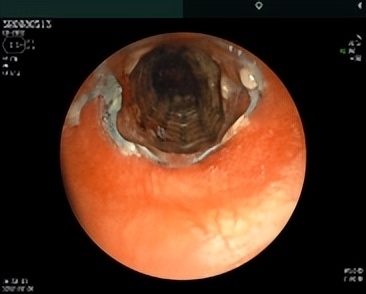

(术后第五天)

术后,患者状态良好,她激动地说:“之前呼吸感觉像被人掐住脖子,憋闷得难受,现在顺畅多了,心里一下子就踏实了。”患者家属也满是感慨:“真没想到在家门口的医院就能完成这么高难度的手术,多亏了医生们的精湛医术,太感谢你们了!”